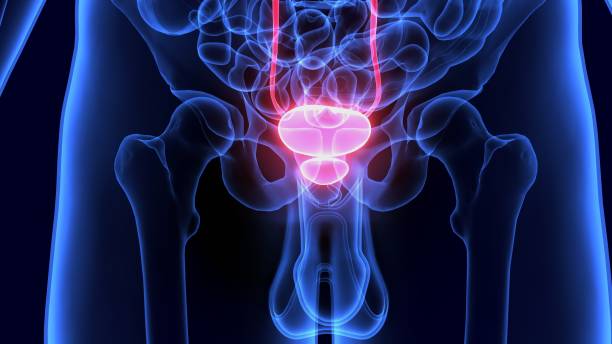

남성 생식기의 요로계와 직접적 연관이 있는 전립선은 사과 모양으로 배꼽 아래쪽에 위치해 있으며 상당히 중요한 역할을 하고 있습니다. 전립선은 사정을 조절하고, 정자의 움직임을 돕는 전립선 분비액을 만들어냅니다. 이 분비액은 정자의 영양 공급과 이동에 필수적인 성분을 포함하고 있습니다. 또한, 전립선은 방광을 둘러싸고 있는 방광 경화근과 골반 바닥 근육에 대한 지지 구조 역할을 할 수 있어 상당히 중요하나 전립선에도 암이 발병될 수 있어 초기에 원활한 대응을 해야만 합니다. 그럼 이번 시간에는 전립선암 초기증상에 대해 자세히 정리해보겠습니다.